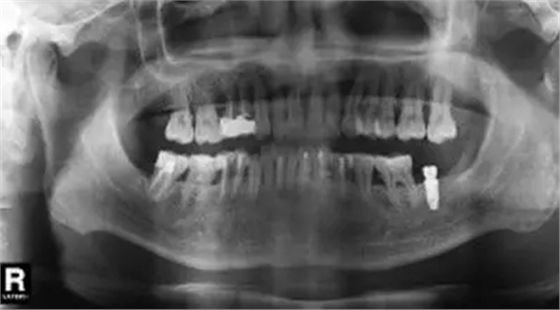

臨床檢查47面見大面積充填物,冠近遠中折裂,叩痛(+),松動度(-),牙齦(-)。曲面體層片示46髓腔內(nèi)及根管見高密度影像,根尖未見明顯陰影(圖6)。

圖6 拔除47前曲面體層片